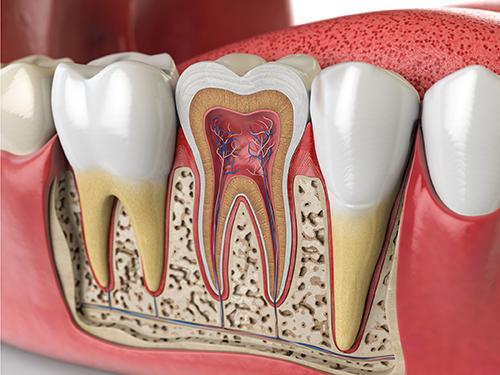

치아 신경치료란

안녕하세요 목동안치과의 안상우 원장입니다.오늘은 치과병원에서 하는 신경치료에 대해서 알아보려고 합니다.치과에서 신경치료를 받는다는 이야기를 들어 본적이 있으실꺼에요. 신경치료라는것이 신경을 치료하는것인가? 라고 생각할수 있습니다.치과의 신경치료는 일반적인 분들이 생각하는 신경치료와 약간 다릅니다.치아안에는 신경이 들어 있습니다. 이 신경은 차갑거나 뜨거운 온도를 느낄수 있으며 충치등으로 인해서 신경에 염증이 발생하게 되면 압력이 올라가면서 통증이 유발되게 됩니다.보통의 치료라고 하면 치료후에 조직이 원상태로 돌아오는것을 생각하는 분들이 많습니다. 하지만 치과에서 하는 신경치료는 병적인 치아안의 신경을 제거하는 술식이에요.통증을 유발하는 신경자체가 제거되기 때문에 통증이 느껴지지 않도록 하는것이지요신경을 제거한다고 하니깐 먼가 무서운 느낌이 드실수 있는데 실제로 치아안의 신경은 쓰임새가 그렇게 많지는 않아요.온도 변화를 느낀다고 말씀드렸는데 치아의 신경으로 음식의 온도를 느끼면서 먹는 사람은 거의 없거든요?치아안에는 신경이 불필요하게 많이 있어서 치아에 생긴 통증은 그 강도가 매우 큰경우가 많습니다.그럼 신경치료는 어떻게 진행되는걸까요?신경치료는 보통 3~4회로 진행이 됩니다.신경을 제거할때는 치과용 도구와 약품을 이용하게 되는데 쉽게 말해서 락스성분의 약품을 이용하게 됩니다.치아안의 신경관은 유기 물질로 이루어져 있기때문에 치과도구로 이 신경조직을 제거 하고 락스성분인 약품으로 남은 신경조직을 녹여서 제거하게 되요.신경치료 약속은 보통 3~4일간격으로 받게 됩니다.두번째날에도 신경을 제거 하는데 대부분 첫날에 신경을 많이 제거해 놨기 때문에 남은 조직들을 더 제거 하고 첫날 못찾았던 신경관이 발견되거나 하면 그쪽도 청소를 하게 되요.이렇게 신경이 제거되고 통증이 없어지게 되면 세번째 날에는 신경치료를 마무리 하게 되는데 청소하고 소독된 신경관에 치과약제를 채우고 마무리 하게 되요.마무리된 치아는 후에 보철치료라고 하는 크라운 치료를 받게 됩니다.신경치료를 해서 치아의 신경이 제거된다면 치아가 감각이 없어진다고 생각하실수도 있습니다.하지만 그렇지는 않아요. 치아에는 치아안에 있는 신경도 있지만 치아 뿌리를 둘러 쌓고 있는 치주인대가 있어서 치아에 가해지는 교합력을 느끼게 됩니다.소위말하는 씹는 맛이라는것은 치아안의 신경보다 치주인대로 느끼게 되요.따라서 치아의 감각이 완전히 없어지는 것은 아니며 음식을 먹는 느낌은 가지게 됩니다.신경치료를 한 상태에서는 치아가 약해져 있기 때문에 일반적으로 떼우는 것보다는 씌우는 크라운이라는 치료를 하게 되요.